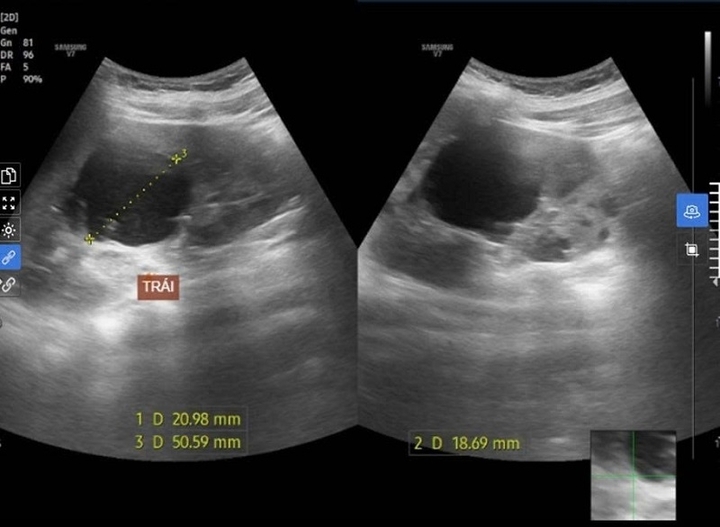

Kết quả cho thấy thận hai bên xuất hiện nhiều nang (thận trái >7 nang, thận phải >10 nang), kích thước thận to hơn bình thường. Dù chưa có biểu hiện suy thận (Creatinin: 53.16, eGFR: 195 ml/ph/1.73 m²), song em được chẩn đoán mắc bệnh thận mạn giai đoạn 1 – giai đoạn sớm nhất, chưa gây tổn thương chức năng thận.

Hình ảnh nang thận trái của nam bệnh nhân ghi nhận trên siêu âm.